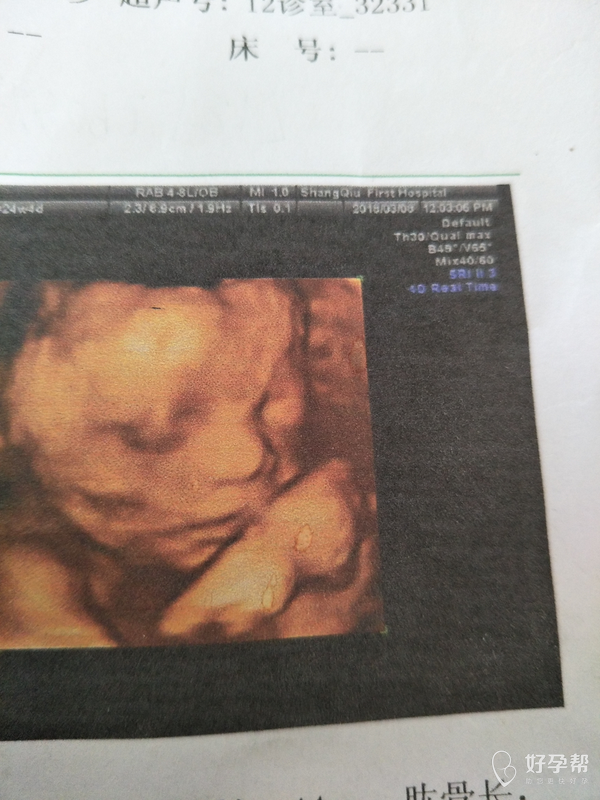

医生帮我看看这个图片上得嘴唇,往右一点那是什么,是模糊造成的还是什么

你好,影像学图片,是模拟成像。受子宫壁胎盘的影响,上唇连贯,脸部的阴影是成像造成的。

右边嘴唇能看的清吗?